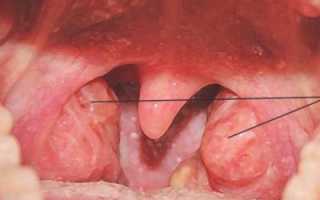

Главными симптомами воспаления являются следующие:

- затрудненное дыхание через нос,

- вынужденное дыхание через рот, что способствует возникновению проблем со сном,

- ощущение дискомфорта и неудобства при глотании еды,

- недостаточное кровоснабжение тканей кислородом, что приводит к задержке умственного развития.